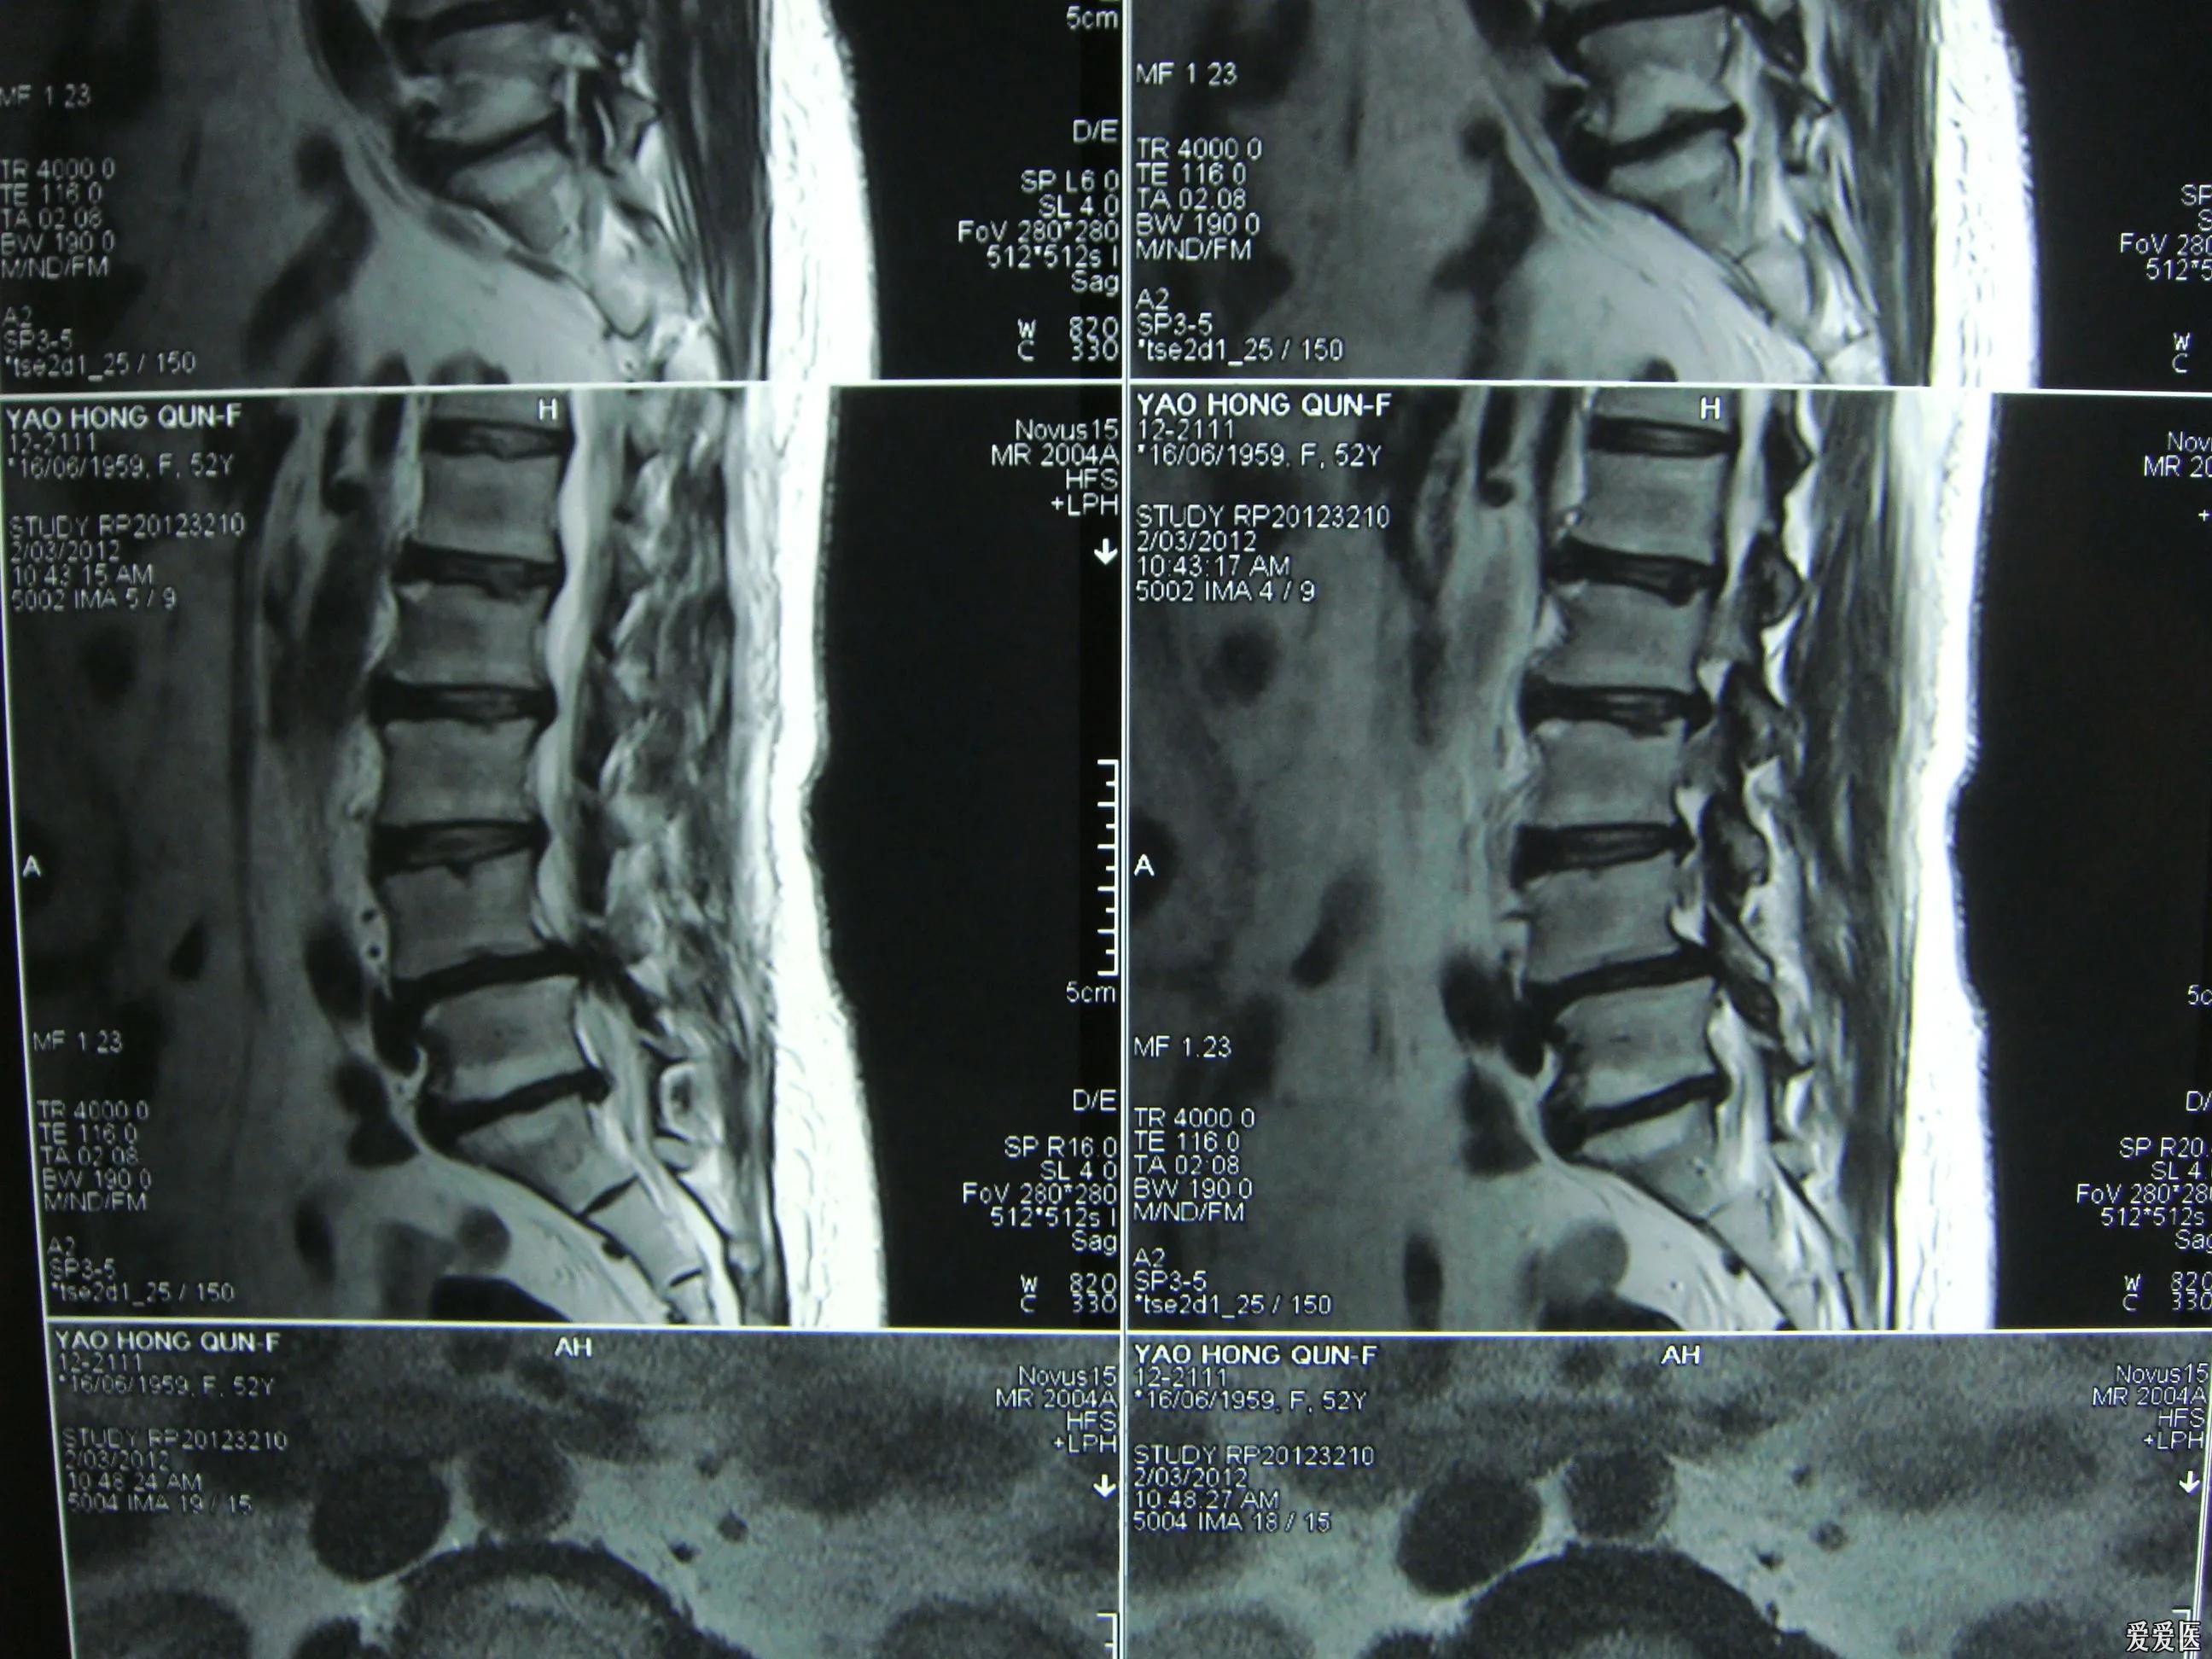

【腰痛反复】

疼痛反复发作是腰椎间盘突出的一个特点,腰痛腿麻,站不直,周而复始,究其原因,主要还是受凉和弯腰有力,久坐太久,无菌性炎症水肿加重,腰部损伤增生,加重神经卡压,腰突反复,反复不断,苦不堪言。